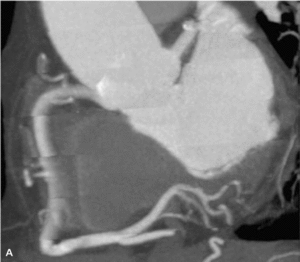

RYCINA 1. Badanie wykonane protokołem SnapShot Freeze GE Healthcare, zmniejszającym artefakty ruchowe wynikające z ruchu tętnic wieńcowych.

4. Wprowadzenie śledzenia ruchu tętnic wieńcowych podczas badania, aby uniknąć artefaktów ruchowych (ryc. 1).